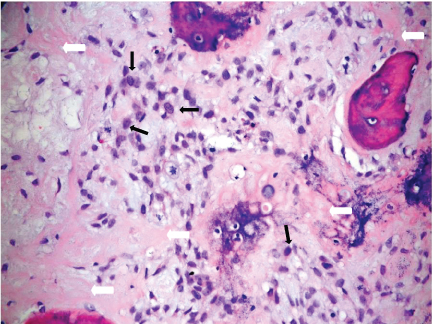

Based upon these MR imaging features, the differential diagnoses were osteosarcoma and lymphoma. Infective process was less likely as the end-plates and the adjacent discs were preserved and the patient did not have clinical signs of infection and the laboratory findings excluded infections such as bacterial, fungal and tuberculous infections. A computed tomography (CT)- guided biopsy of T9 vertebral body was performed on the same day as the MR Imaging but was not diagnostic. The patient remained neurologically well up to one week after the first MR imaging. The patient's gait then became more unsteady with occasional falls, and increasing weakness of the lower limbs. Open biopsy of T9 spinous process was performed 11 days later. This showed a tumour composed of atypical spindle cells which produced osteoid and which permeated the marrow spaces extensively, consistent with a high-grade osteosarcoma (Figure 4).

Figure 4: Photomicrograph of the T9 vertebral biopsy specimen shows atypical spindle cells (thin black arrows) producing osteoid (thick white arrows) with permeation into marrow spaces. Consistent with high-grade osteosarcoma (Haematoxylin & eosin, x200). View Figure 4